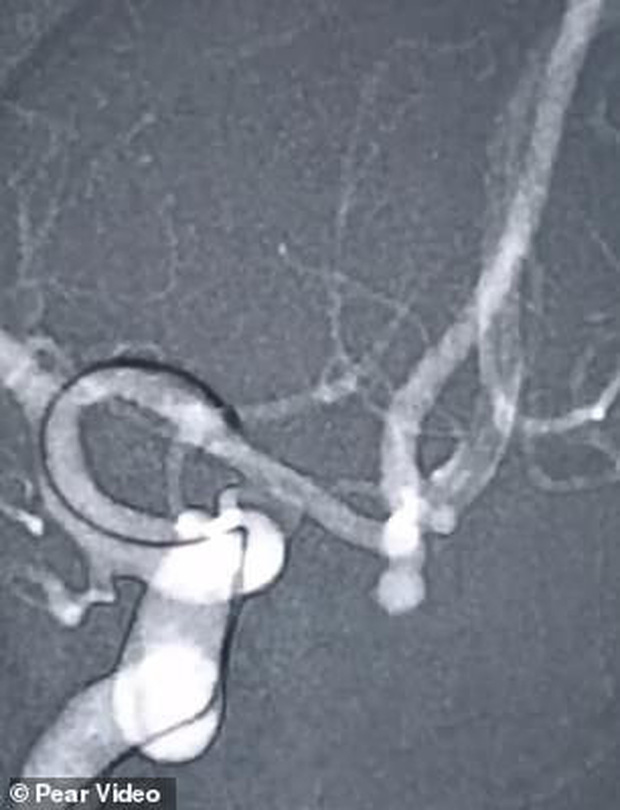

Sau khi tiến hành chụp CT, các bác sĩ phát hiện bà Zhang có vết vỡ động mạch 2,5mm.

Theo các bác sĩ, bà Zhang đã bị phình động mạch não suốt một thời gian dài nhưng không có triệu chứng gì. Trước đó, bà Zhang có tiền sử bệnh huyết áp và tiểu đường.

Chỉ đến khi gồng mình hát nốt cao, đoạn phình động mạch của bà Zhang mới bục vỡ.

“Bệnh phình động mạch thường không có triệu chứng nào nghiêm trọng”, bác sĩ Jin nói. “Nhưng một khi động mạch bị vỡ, người bệnh sẽ đối mặt với nguy cơ tử vong lên tới 30%.”

“Các môn thể thao gắng sức, hoặc việc hát hò có thể khiến động mạch bị phình bục vỡ”, bác sĩ nói thêm.